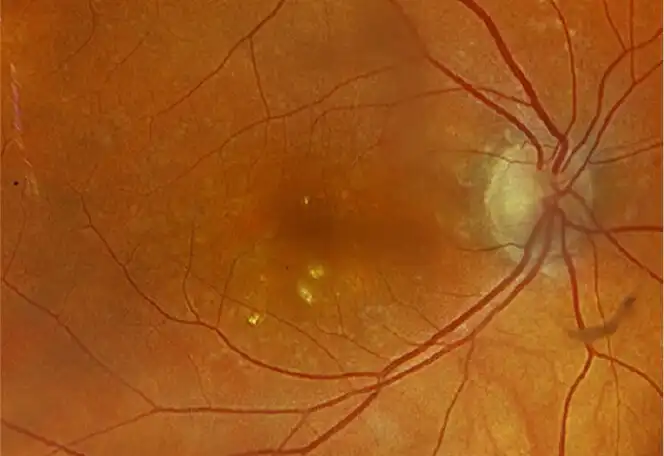

IZERVAY™ (avacincaptad pegol intravitreal solution) is indicated for the treatment of geographic atrophy (GA) secondary to age-related macular degeneration (AMD)